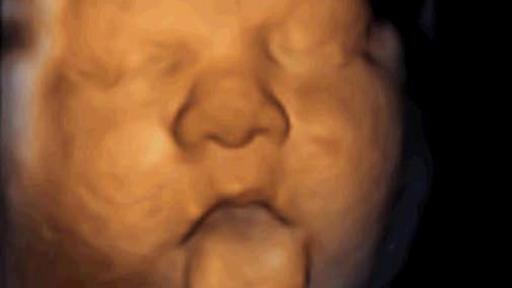

Maastricht, 15 June 2016 -. The foetus moves its mouth in an exaggerated manner when it hears a human voice. This occurs from the 16th week of pregnancy (with a foetus of 11cm) and only when the voice reaches it through an intravaginal device developed for this purpose. This is one of the conclusions of the study presented by Dr. Álex García-Faura, the Scientific Director of the Institut Marquès, at the 25th European Congress of Perinatal Medicine held in Maastricht (Netherlands).

“Foetuses react with vocalisation movements when we can reach them with voice messages through their mother’s vagina. The response is different when we emit music and we put this down to music and voice activating different brain circuits: music activates neuronal circuits that trigger emotions”, says Dr. García-Faura, who has compared the differing reactions by using transabdominal ultrasounds. Accordingly, 70% of foetuses move their mouths when they are talked to; when they hear music they make more complex movements that also include the protrusion of their tongues.